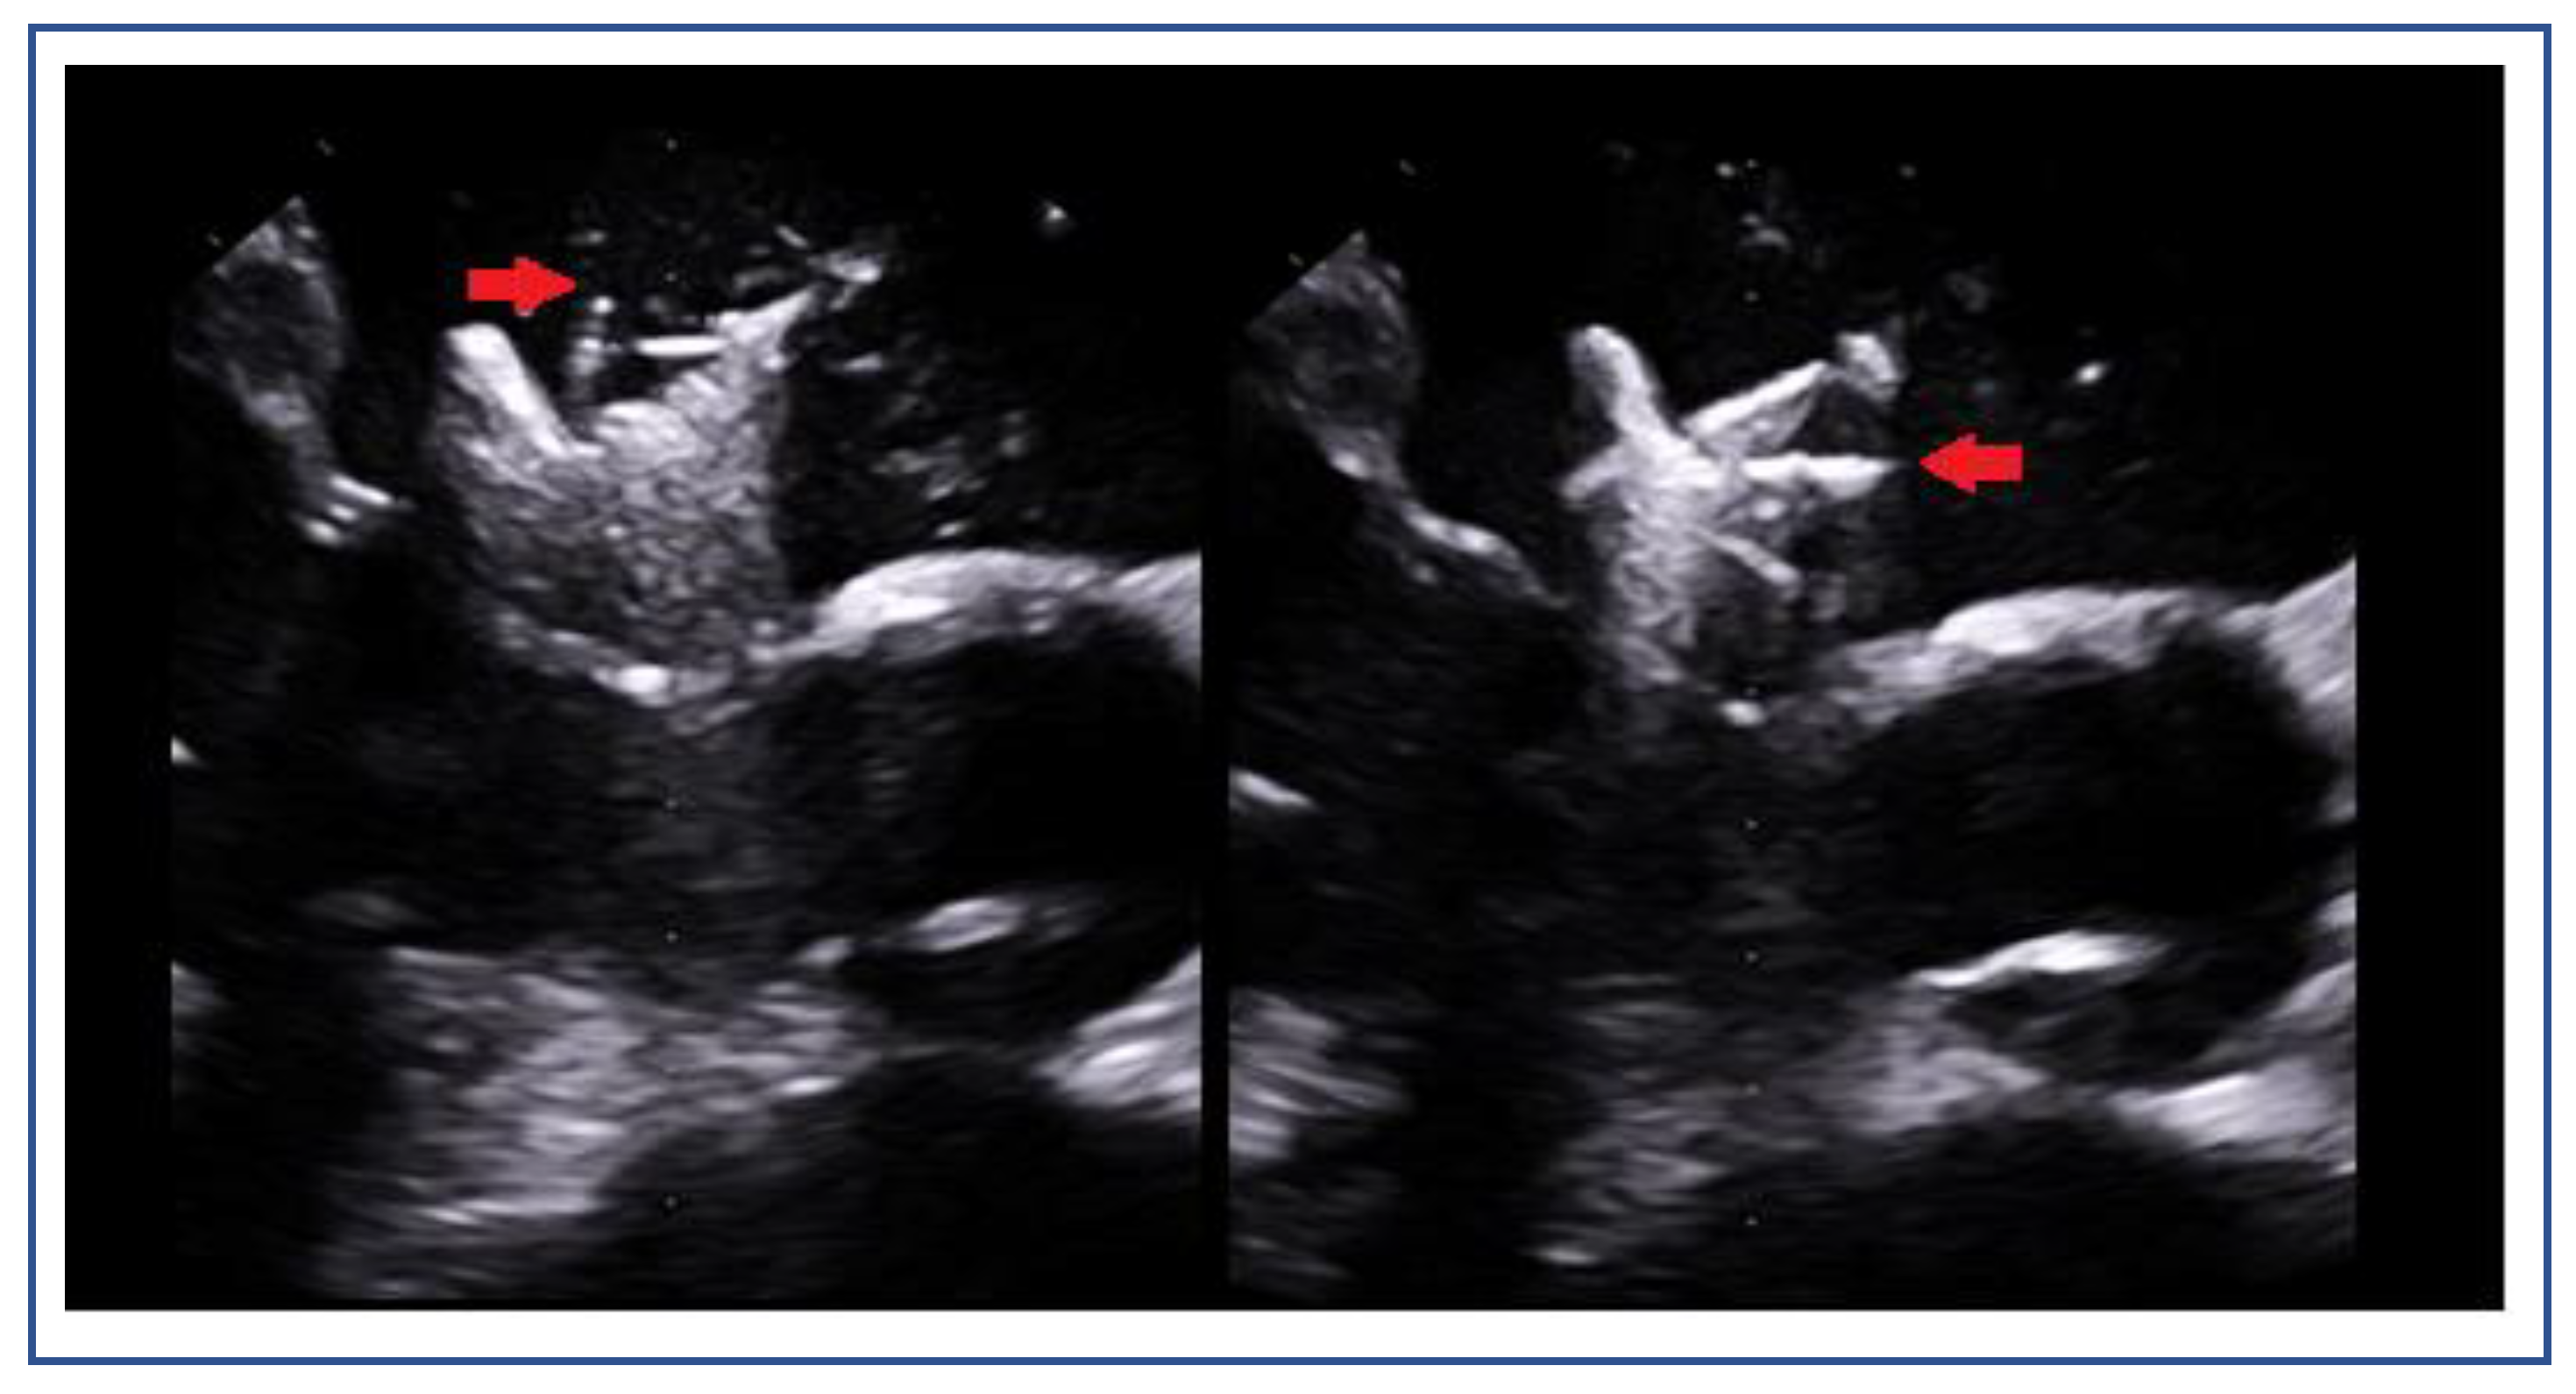

Posterior Leaflet Cleft-like IndentationThe posterior leaflet normally has two indentations that differentiate the scallops. A cleft-like indentation is defined as having a depth of at least 50% of the adjacent scallops [37,38] and 3D imaging is the best option to recognize such abnormalities (Figure 9). This feature makes grasping challenging and may lead to residual mitral regurgitation (MR).

Adequate but Tethered LeafletsPosterior leaflet length may be sufficient, but severe tethering reduces coaptation and grasping success (Figure 11).